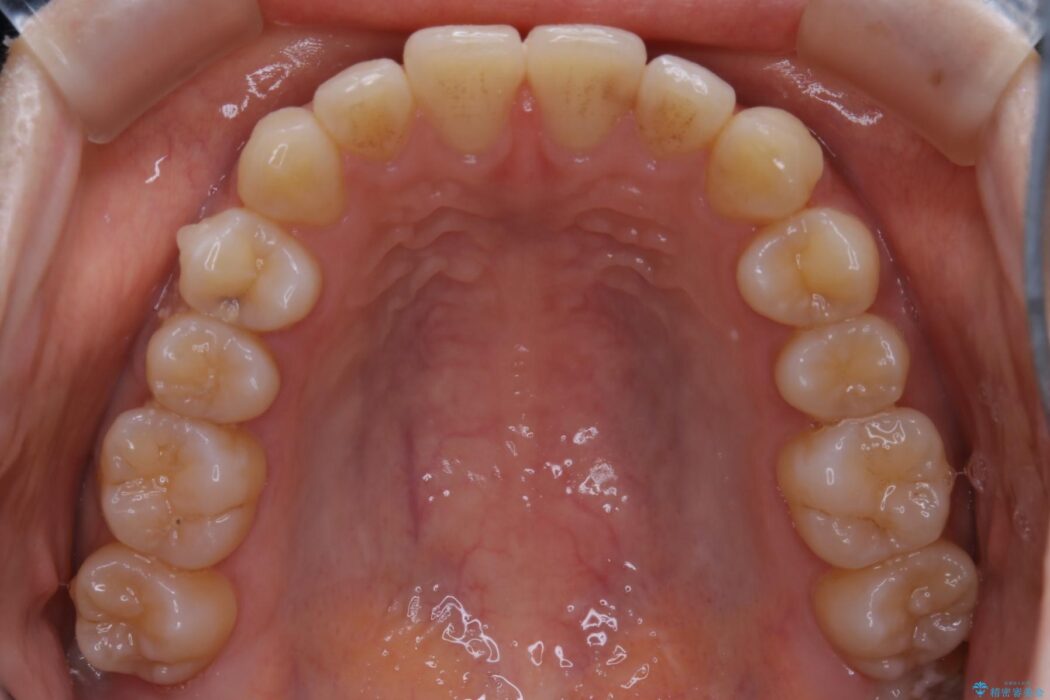

検査をしたところ奥歯の噛み合わせなどに問題が見られなかったため、軽度のねじれがある下顎前歯に焦点を当てた部分矯正の適応が可能と判断し、インビザラインのライトパッケージをご提案しました。

本症例では奥歯に関して問題がほぼ見られなかったため、部分矯正を行うことが可能と判断しました。

通常の全体矯正と比べピンポイントの部分矯正となると、動かす歯が少なくなるため治療期間が格段に短くなり、費用が抑えられることがメリットとして挙げられます。